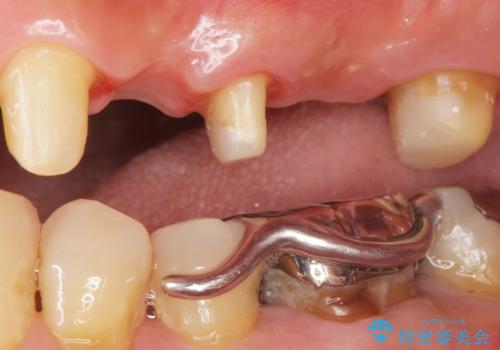

- 左上の歯ぐきが腫れていることを主訴に来院された患者様です。

精査したところ、歯ぐきが腫れている左上の小臼歯(左上4)は保存不可能な状態でした。

保存不可能な歯(左上4)を抜去後、ブリッジによる補綴治療を行いました。